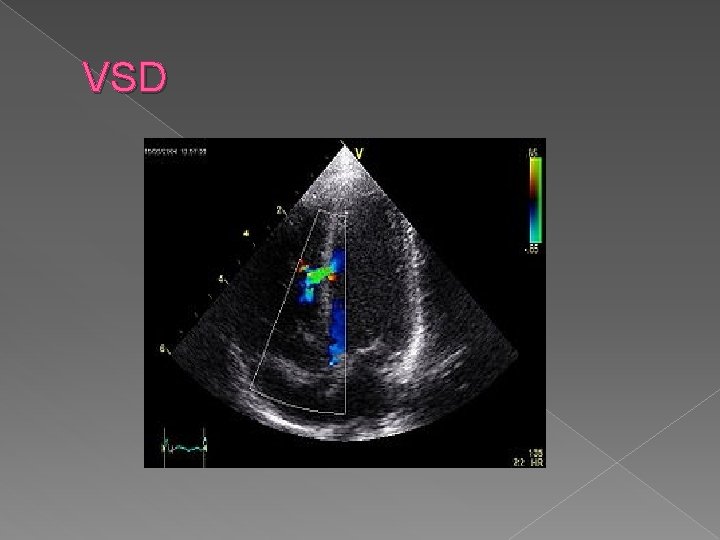

Sonographic findings: � Demonstration of an opening between the ventricles on 4 chamber view � Bidirectional flow demonstrated with color Doppler � Larger defects are easier to diagnosis.

Ventricular septal defect (VSD) › Ranks first in frequency of all cardiac anomalies › Opening between the two ventricles › Commonly caused by a teratogen-associated fetal defect. › Associated with other cardiac anomalies 50% of the time. › Seen by demonstrating an opening between the ventricles on a 4 chamber view

VSD

VSD